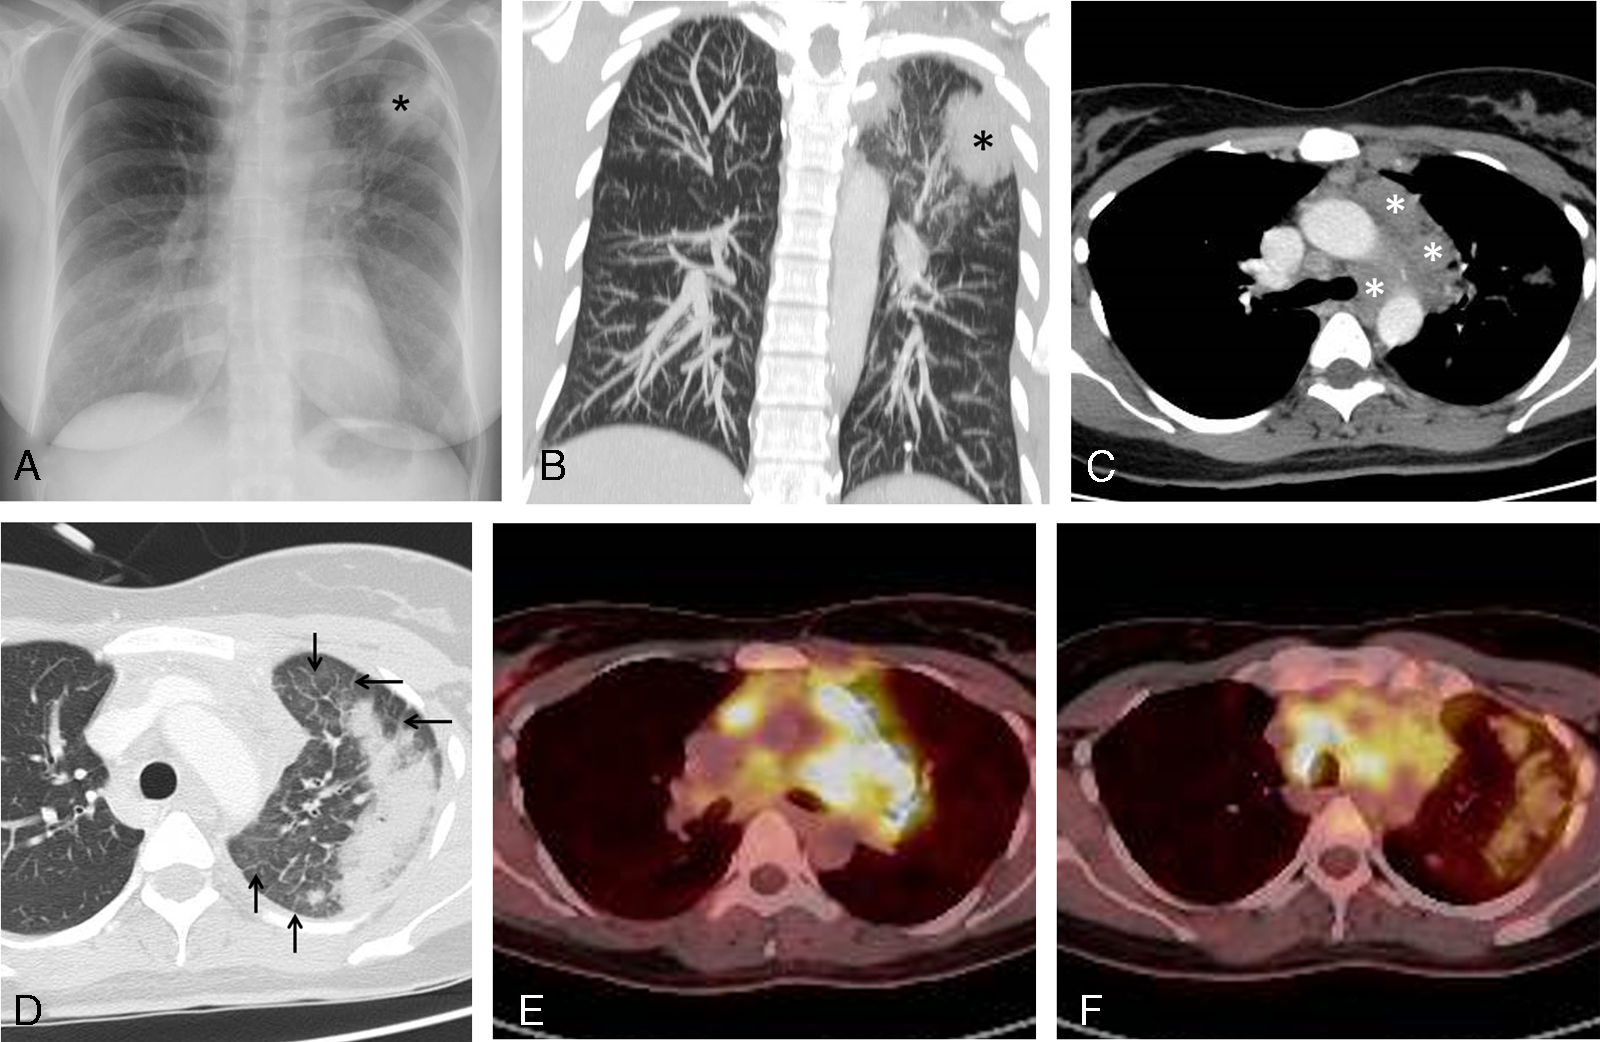

Medicina Clínica Hodgkin disease presenting as hemoptysis and mimicking lung cancer

Hodgkin disease presenting as hemoptysis and mimicking lung cancer

Hemoptisis como forma de presentación de un linfoma de Hodgkin que simula un cáncer de pulmón